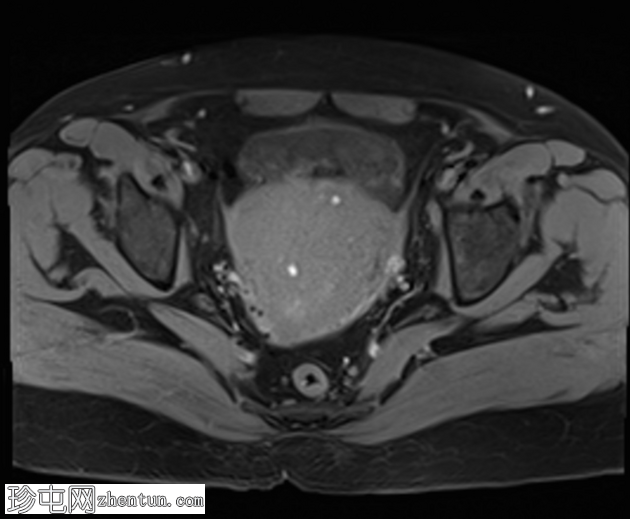

冠状位

T2加权像

子宫增大,交界区弥漫性增厚,厚度约2.5 cm,边界模糊,在T1加权像和T2加权像上均可见无数点状高信号灶,提示出血灶。

在预期的膀胱尿道区域可见一小片异常信号强度的局灶性区域,T2加权像呈高信号,提示膀胱尿道子宫内膜异位症。

盆腔影像学检查(超声或MRI)通常显示局灶性或弥漫性、常不对称的子宫肌层增厚,并伴有异质性影像。

我们报告一例50岁女性患者,其超声和MRI影像均表现出弥漫性子宫腺肌症的特征性表现。